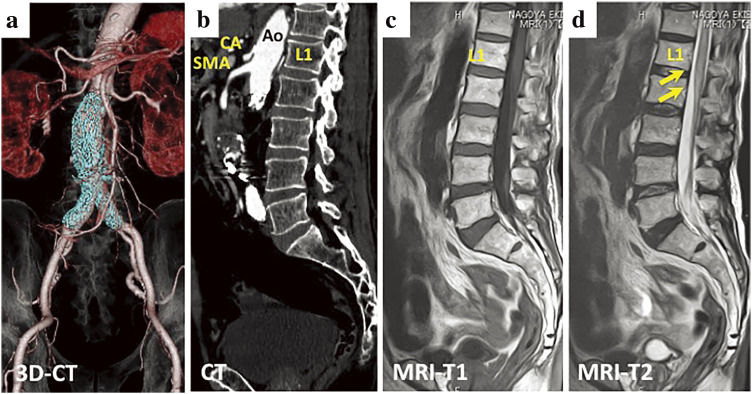

脊髓梗死(SCI)是腹主动脉瘤(AAA)血管内主动脉修补术(EVAR)的一种罕见但严重的并发症。这种并发症难以预测、预防和治疗,并可能导致严重的功能障碍。我们描述了一例患者的病例,该患者在肾下动脉瘤 EVAR 术后不久出现截瘫和下肢热痛功能障碍。在确诊 SCI 后,我们立即启动了脑脊液引流,给予类固醇、纳洛酮和自由基清除剂,并维持高血压。然而,患者的症状并没有得到充分改善。由于存在 SCI 的可能性,因此应立即开始治疗。

Spinal cord infarction (SCI) is a rare but serious complication of endovascular aortic repair (EVAR) for abdominal aortic aneurysms (AAA). It is difficult to predict, prevent, and treat and can cause significant impairment. We describe the case of a patient who experienced paraplegia and thermal pain dysfunction of the lower extremities shortly after EVAR for an infrarenal AAA. Immediately after confirming SCI, we initiated cerebrospinal fluid drainage, administered steroids, naloxone, and free radical scavengers, and maintained high blood pressure. However, the patient's symptoms did not improve sufficiently. Since the possibility of a SCI exists, prompt treatment should be initiated.